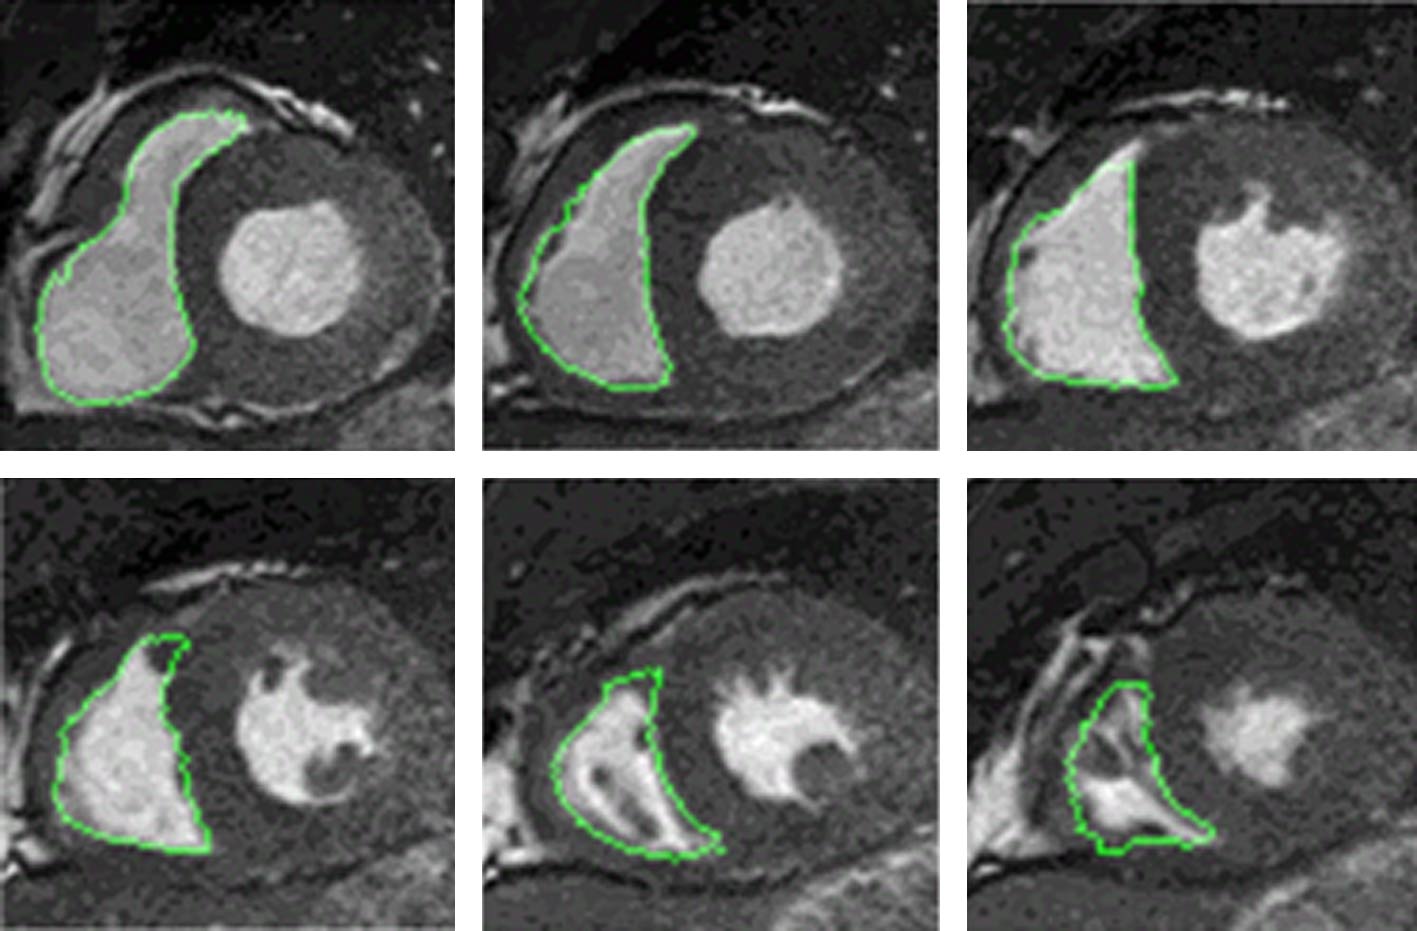

Segmentation of right ventricle (RV) in a cine cardiac magnetic resonance (CMR) image is essential for the diagnosis and therapy of cardiac diseases. Traditional image segmentation methods fail to achieve high accuracy due to the complex structure of RV. Multi-atlas frame, which transforms the segmentation into registration and fusion, has become one of the main segmentation methods of RV in recent years. In this paper, we suggest a new multi-atlas frame for the automatical and accurate segmentation of RV. Firstly, an adaptive affinity propagation algorithm is used to obtain a series of atlases, in which the atlas set most similar to the target image based on hausdorff distance and normalized mutual information is selected. Then, the target image is registered onto the selected atlas by using multi-resolution strategy-based affine transform and Diffeomorphic demons algorithm to generate a deformation field, which is applied to the label image to obtain coarse segmentation results of RV. Finally, the Consensus Level, Labeler Accuracy and Truth Estimation (COLLATE) algorithm is used to fuse the coarse segmentation result to obtain the RV. The 30 cine CMR datasets are applied to the retrospective analysis. The comparison between RV value from the present algorithm and that from the manual segmentation shows that the average dice index and hausdorff distance are 0.84 and 11.46 mm, respectively, the correlation coefficients and deviation means of endo-diastolic volume, endo-systolic volume and ejection fraction are 0.94, 0.90, 0.86, and 2.5113, –3.4783, 0.0341, respectively. Compared with convolutional neural networks, the new multi-atlas frame has an endo-systolic volume close to the manual result. The results show that the suggested method improves the accuracy and robustness of segmentation of RV from the effective atlas selection and multi-resolution Diffeomorphic demons algorithm-based registration, and it promises to be applied to clinical diagnosis.